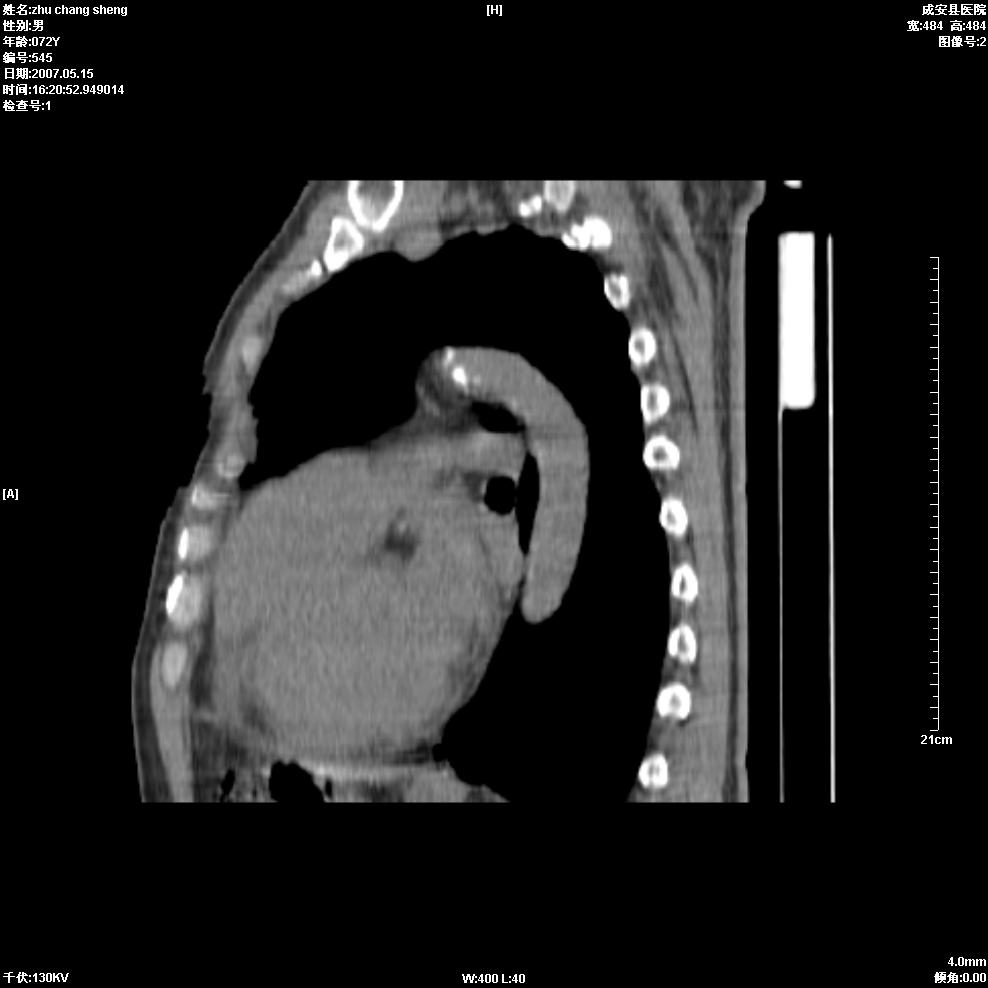

以下是引用医博云天在2007-5-15 19:10:00的发言:[br]心包积液,胸腔积液,心影增大,左心为主。

以下是引用zhangzhongshou在2007-5-15 20:21:00的发言:[br]心包积液可以肯定有,肿块显示不清,建议增强或mri检查。

以下是引用jinning在2007-5-15 21:06:00的发言:[br]心包积液可以肯定,建议增强或mri检查吧!

以下是引用拾荒者在2007-5-15 22:28:00的发言:[br]心包膜增厚,有少量积液,右室前壁示均匀软组织密度影,边界欠清,建议增强扫描或mri检查与室壁瘤鉴别。

以下是引用还珠格格在2007-5-19 9:50:00的发言:[br]病人与5月18日 做了核磁增强扫描 确诊为前上纵隔侵袭性胸腺瘤。